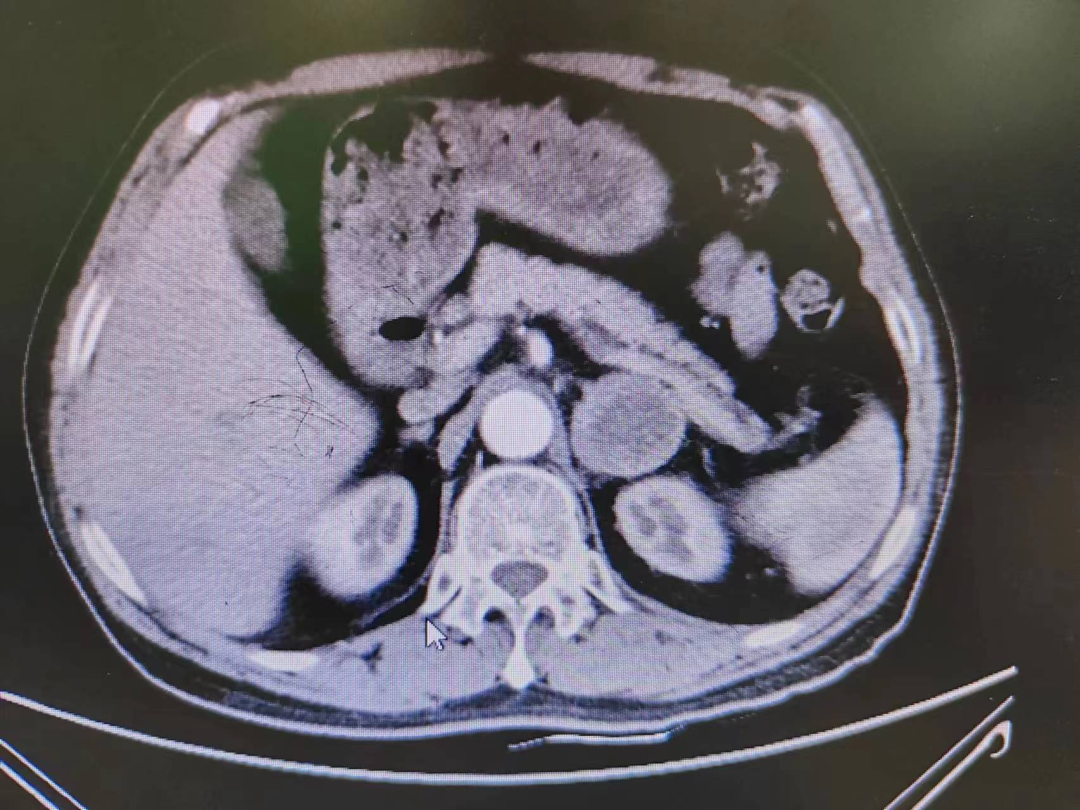

患者熊XX,67歲,因發(fā)現(xiàn)頭暈、頭痛曾多次于外院就診,到新橋醫(yī)院就診完善腎上腺CT考慮嗜鉻細(xì)胞瘤,既往有高血壓病史3年,血壓更高達(dá)230/120mmHg。我院高新區(qū)院區(qū)開診后,患者慕名而來。術(shù)前積極完善血尿兒茶酚胺代謝產(chǎn)物(MNS)均明顯升高,患者于我院高新區(qū)院區(qū)及江南院區(qū)泌尿外科積極控制血壓、心率、血糖,術(shù)前充分?jǐn)U容。

因腫瘤位置位于腎蒂周圍,術(shù)中觸碰腫瘤導(dǎo)致血壓明顯升高,血壓波動(dòng)較大,腫瘤表面血供豐富,不僅需要手術(shù)醫(yī)生豐富的臨床經(jīng)驗(yàn)和高超的技術(shù)水平,也是對(duì)醫(yī)生心理素質(zhì)、勇氣和毅力的嚴(yán)峻考驗(yàn)。